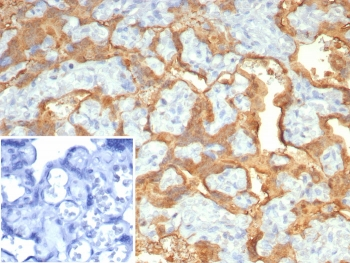

Cathepsin D Antibody

| Description | Cathepsin D Antibody |

| Tested applications | FC, ICC, IHC, IP, WB |

| Reactivity | Human, Mouse |